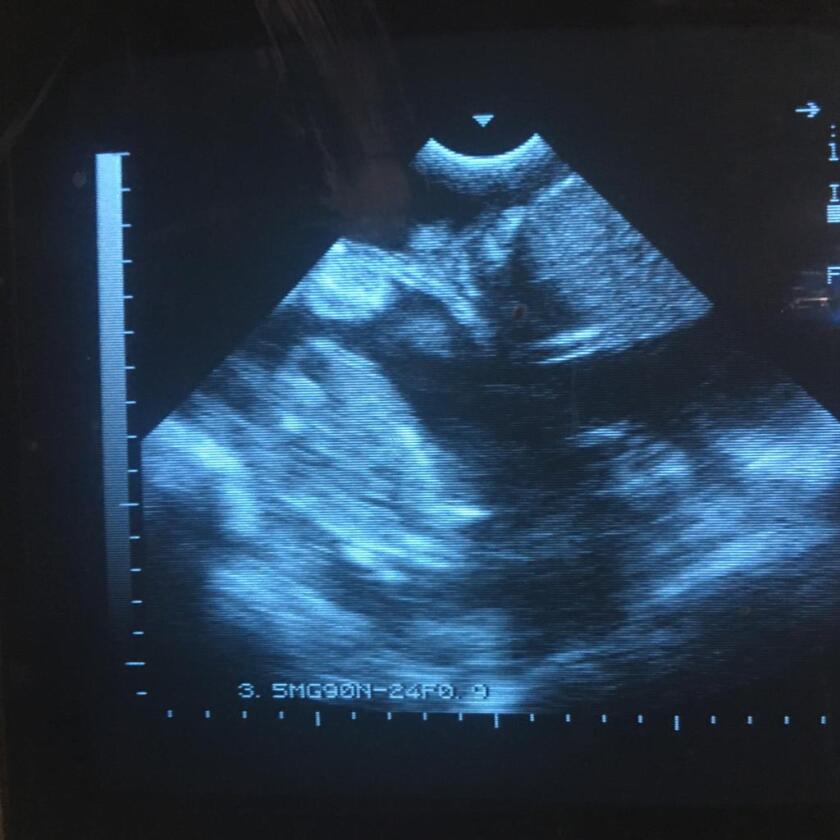

La ecografía es un método sencillo de diagnóstico de gestación y carga fetal, que no sólo determina qué ovejas están gestantes sino la cantidad de fetos que tiene cada una: preñeces simples o múltiples. Además, realizada en el momento adecuado, permite ajustar el manejo nutricional hacia adelante de manera de poder atender de forma diferencial aquellas ovejas de mayores requerimientos.

Las ecografías se realizan vía abdominal, con la oveja sentada o parada en el tubo, brete o cepos específicos facilitan la tarea. Eso es un cambio de paradigma que facilita la adopción de tecnología, porque minimiza los recursos humanos que requiere la ecografía.